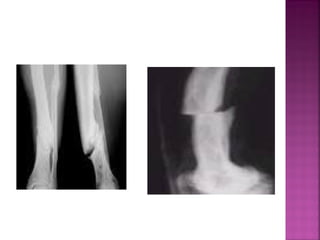

F. TRANSVERSALES

la línea de

fractura es

perpendicular

al eje

longitudinal del

hueso.

F. OBLICUAS

la línea de fractura

forma un ángulo

mayor o menor de 90

grados con el eje

Existen dos líneas de

fractura oblicuas, que

forman ángulo entre si y

delimitan un fragmento

de forma triangular.

Hay múltiples líneas

de fractura, con

formación de

numerosos

fragmentos óseos.